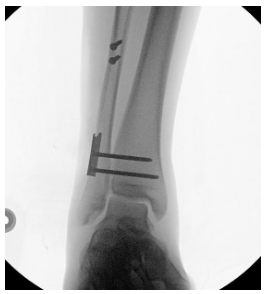

Image H: Fluoroscopy from the OR post-operatively